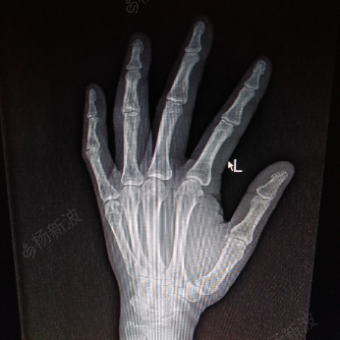

右小指近节指间关节脱位

图片尺寸1000x561